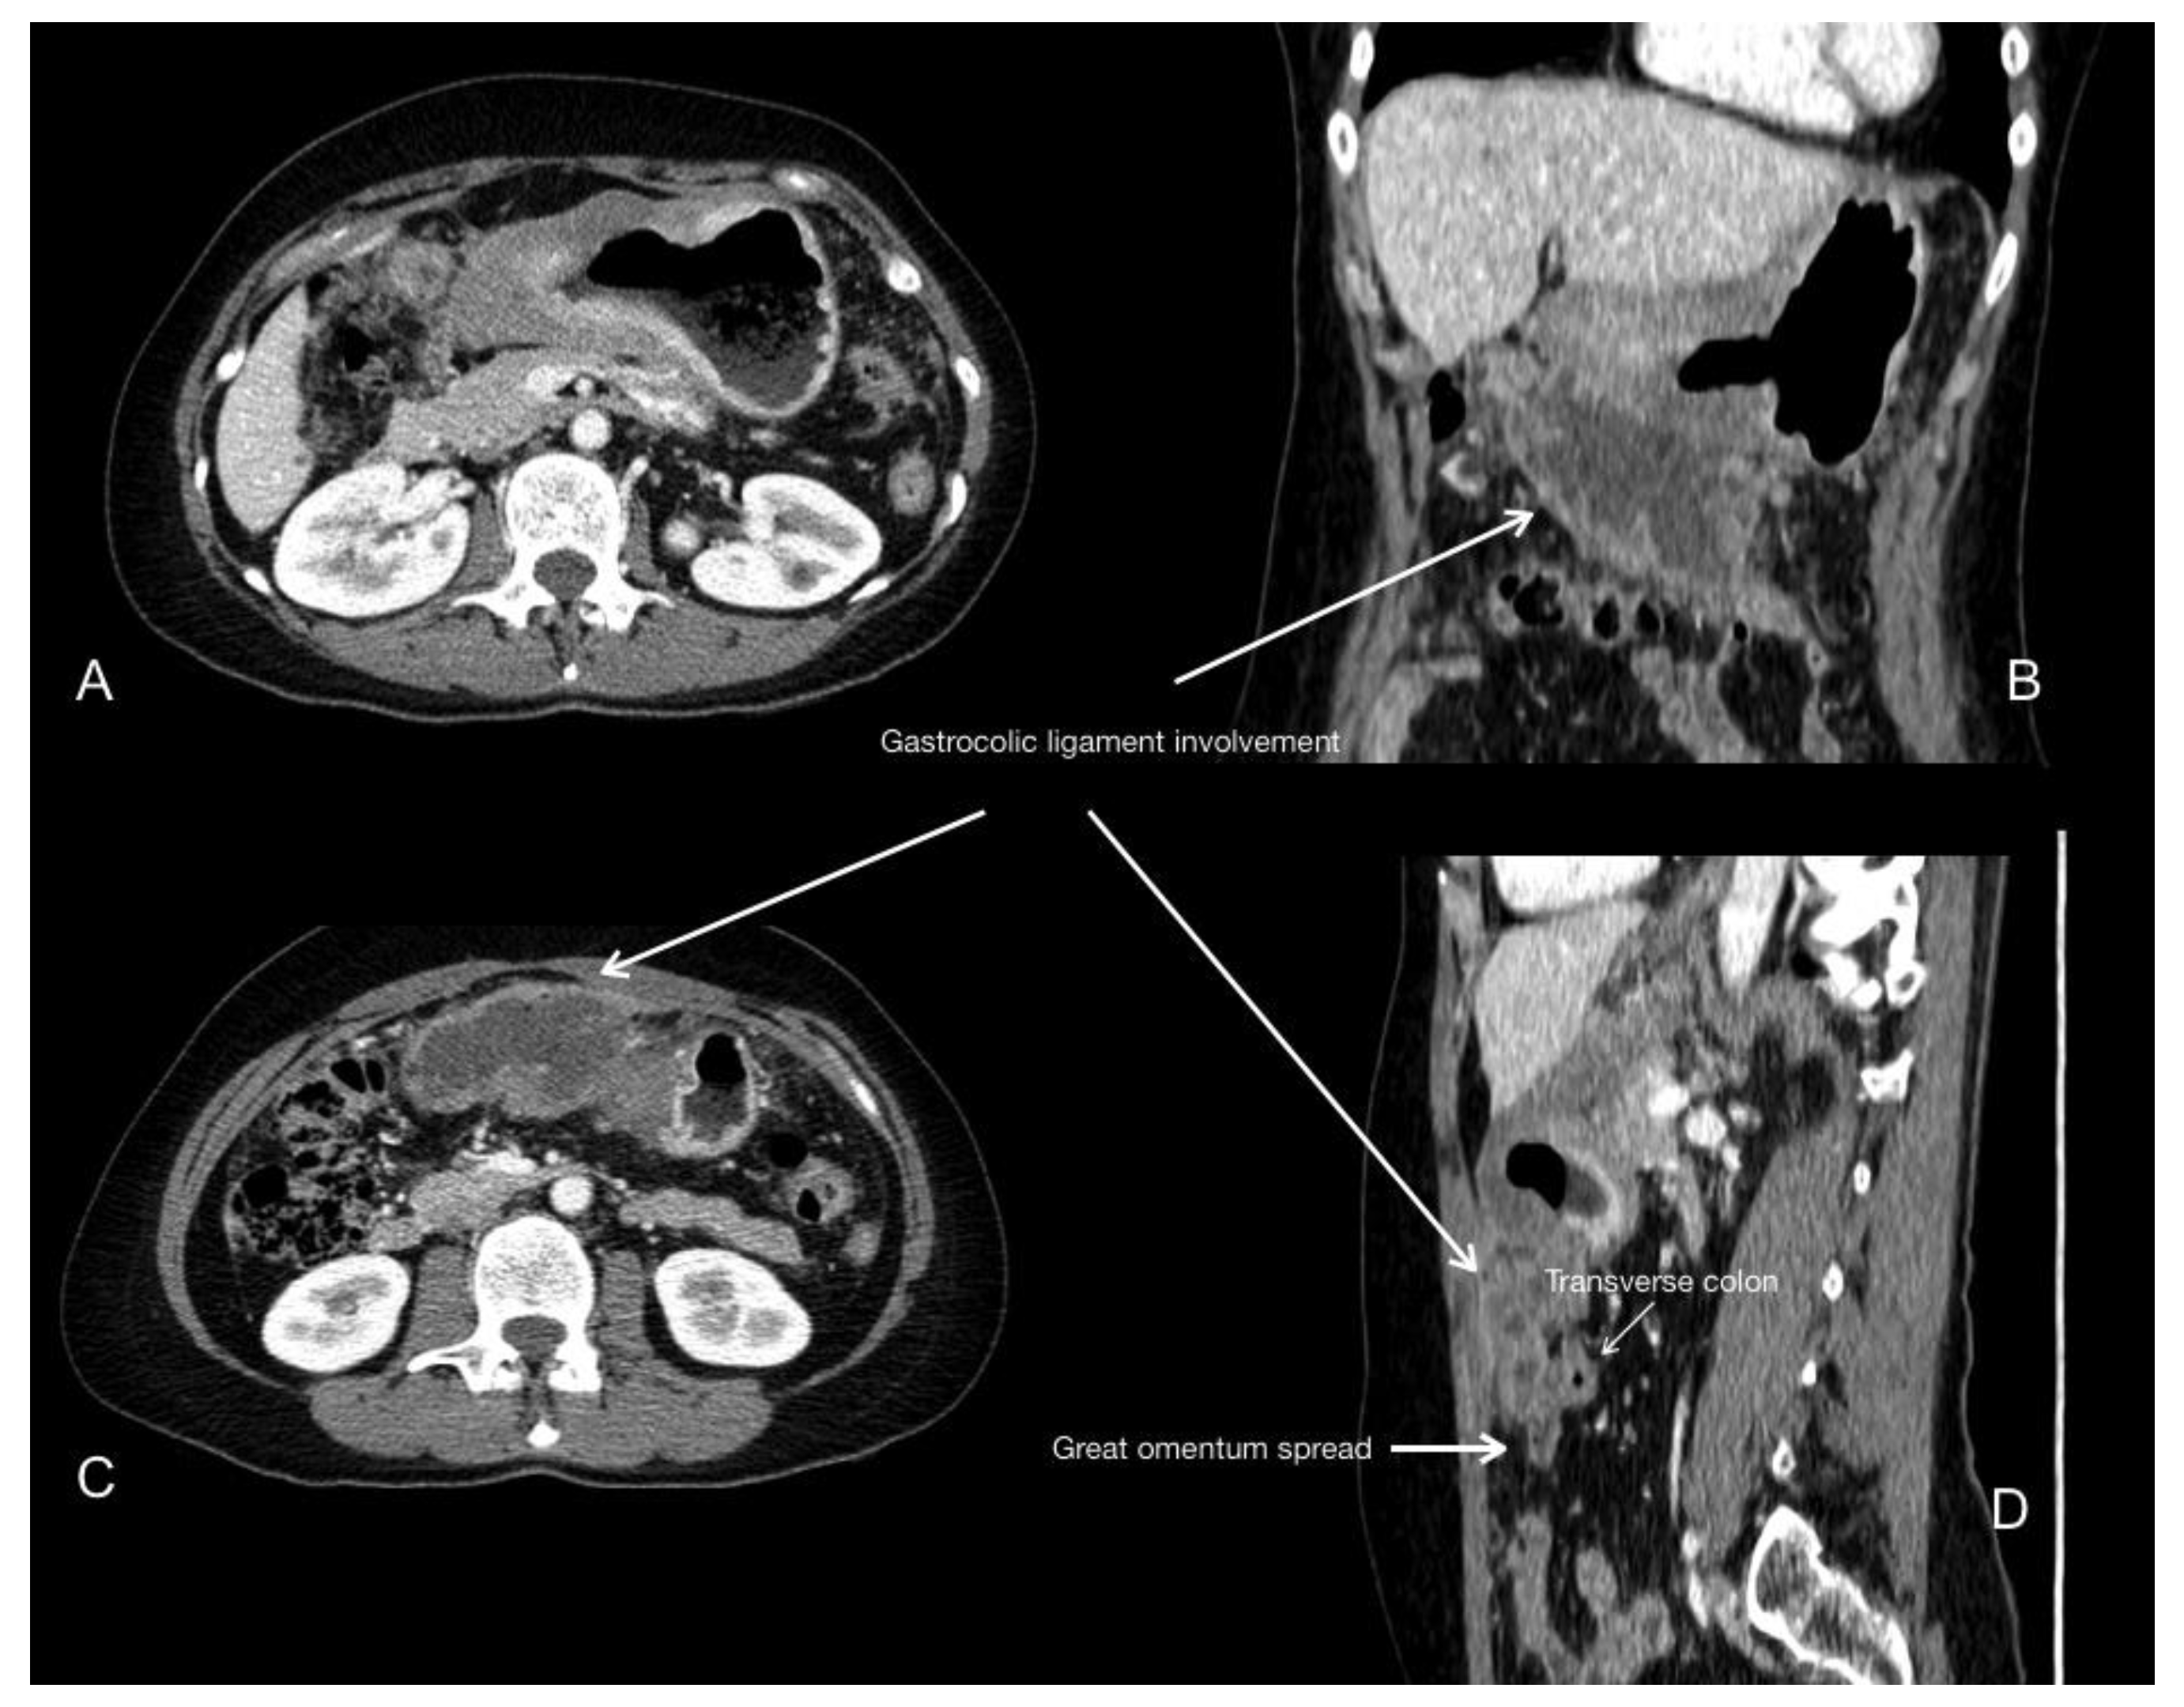

- Young, J.J.; Pahwa, A.; Patel, M.; Jude, C.M.; Nguyen, M.; Deshmukh, M.; Huang, L.; Mohammad, S.F. Ligaments and lymphatic pathways in gastric adenocarcinoma. Radiographics 2019, 39, 668–689. [Google Scholar] [CrossRef] [PubMed]